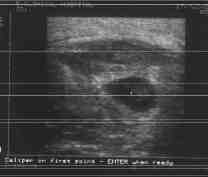

Attached Thumbnails Attached Thumbnails Click image for larger version.

Name:	abscess.jpg

Views:	429

Size:	3.1 KB

ID:	20883

Next day nothing. I work out but i start feeling uncomfortable in the area. Next day a little bump starts to form from one side to the other of my pec. The weekend i helped a friend move and i think it begun to hurt more, it got swollen and moved to the outer side to the armpit. Tuesday i couldnt move my arm at all and i got 39 degrees fever. Wendsday i went to a doctor. It was one that takes care of breasts matters. He made the picture on a echographe, tald me it is an abscess and prescribed antibiotics. If it doesn't start to go away in 5 days it will be opened by a surgeon in order to get all the nasty stuff out.

Doctor said it would be necessary to cut it open and take the residue from the inflamatory process out if it doesnt get smaller in a couple of days. The abscess is the size of a baseball and has the shape of an egg.